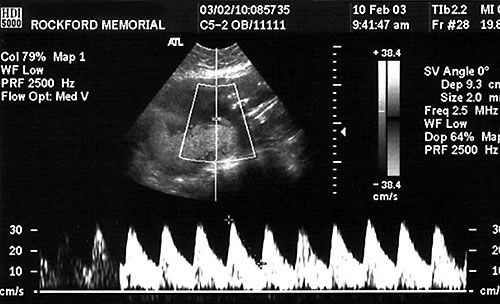

Normal umbilical artery systolic

to diastolic ratio (S/D)

8. Doppler velocimetry:

• Umbilical artery

• Cerebral artery